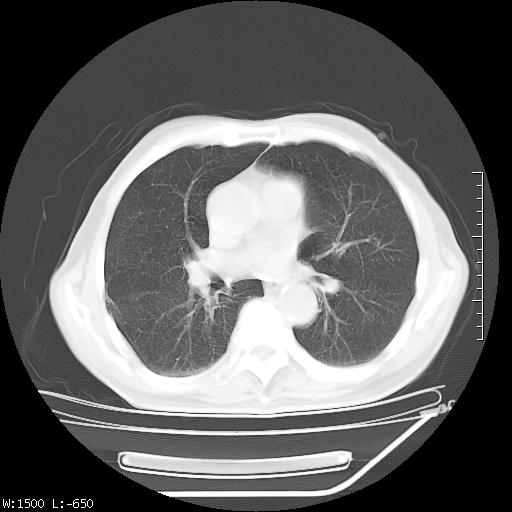

标题: CT23994:男、72、咳嗽、气短两月余,近来消瘦。 [打印本页]

标题: CT23994:男、72、咳嗽、气短两月余,近来消瘦。

tb可能性大(双肺均可见片状密度增高灶,其内可见低密度空洞)。

双肺继发性肺结核

右上肺大片状密度增高影,与胸膜关系密切,内见低密度透亮影,胸膜下可见三角形不张影,左下肺沿支气管走形结节影,纵膈内淋巴结显示。考虑结核并疤痕性不张可能性大,建议穿刺活检,排除肺泡癌。